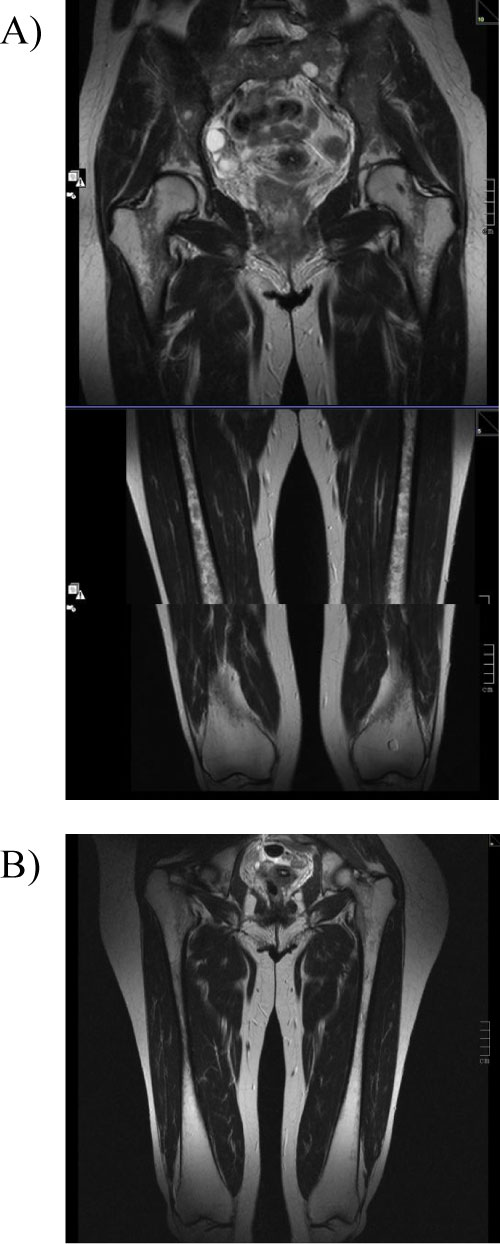

There were clear improvements in the bone components of GD-DS3 such as bone/joint pain and bone marrow infiltration during follow up (Figure 2 and Figure 3). At eliglustat initiation, 3 patients reported moderate or severe bone pain in the previous 30 days, however, at the 6-year follow up these patients reported mild or no/very mild bone or joint pain. Bone marrow infiltration (bone marrow burden [BMB]) was also reduced from marked/severe to moderate in Cases 1 and 2, remained moderate in Case 3 and remained marked/severe in Cases 4 and 5. Prior to eliglustat initiation, Patient 1 had experienced two bone crises in the previous 12 months, whereas no bone crises were reported in any patient following eliglustat initiation.

Figure 3: Coronal T2 - weighted images MR images of bilateral femur.

A) Femur before switch from imiglucerase to eliglustat. Images clearly show diffuse homogeneous hypointensity in diaphysis. BMB score 7 for the femur. B) After 6y of eliglustat therapy. Images After 6y of eliglustat therapy, images indicate BMB score of 4 for the femur. Proximal epiphysis slightly hypointense on T2, indicating a marrow response following medication with eliglustat. Initial Düsseldorf score of 8B improved to 3B after 6 years of treatment (increased bone marrow signal in the tibias [not shown in the present illustration] while both metadiaphysis of the femur are still affected). View Figure 3